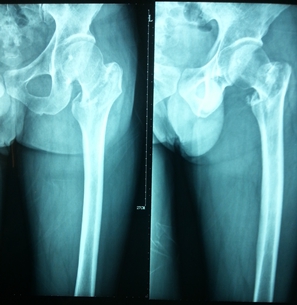

燕化医院开展手术治疗四肢、骨盆骨折患者取得了良好的效果。股骨颈骨折一般以全髋关节置换(THA)和半髋关节置换为主;而对于股骨转子间骨折的外科治疗多采用内固定手术,包括锁定钢板;动力髋系统即DHS、PFN(A)。具有创伤小(微创)、内固定牢固、术后恢复快便于提早下地活动等优点。肱骨、尺桡骨、股骨干、胫骨干的骨折主要采用带锁髓内钉和锁定钢板治疗;复杂的骨盆骨折则采用切开复位,重建钢板治疗。

图1.股骨粗隆部骨折